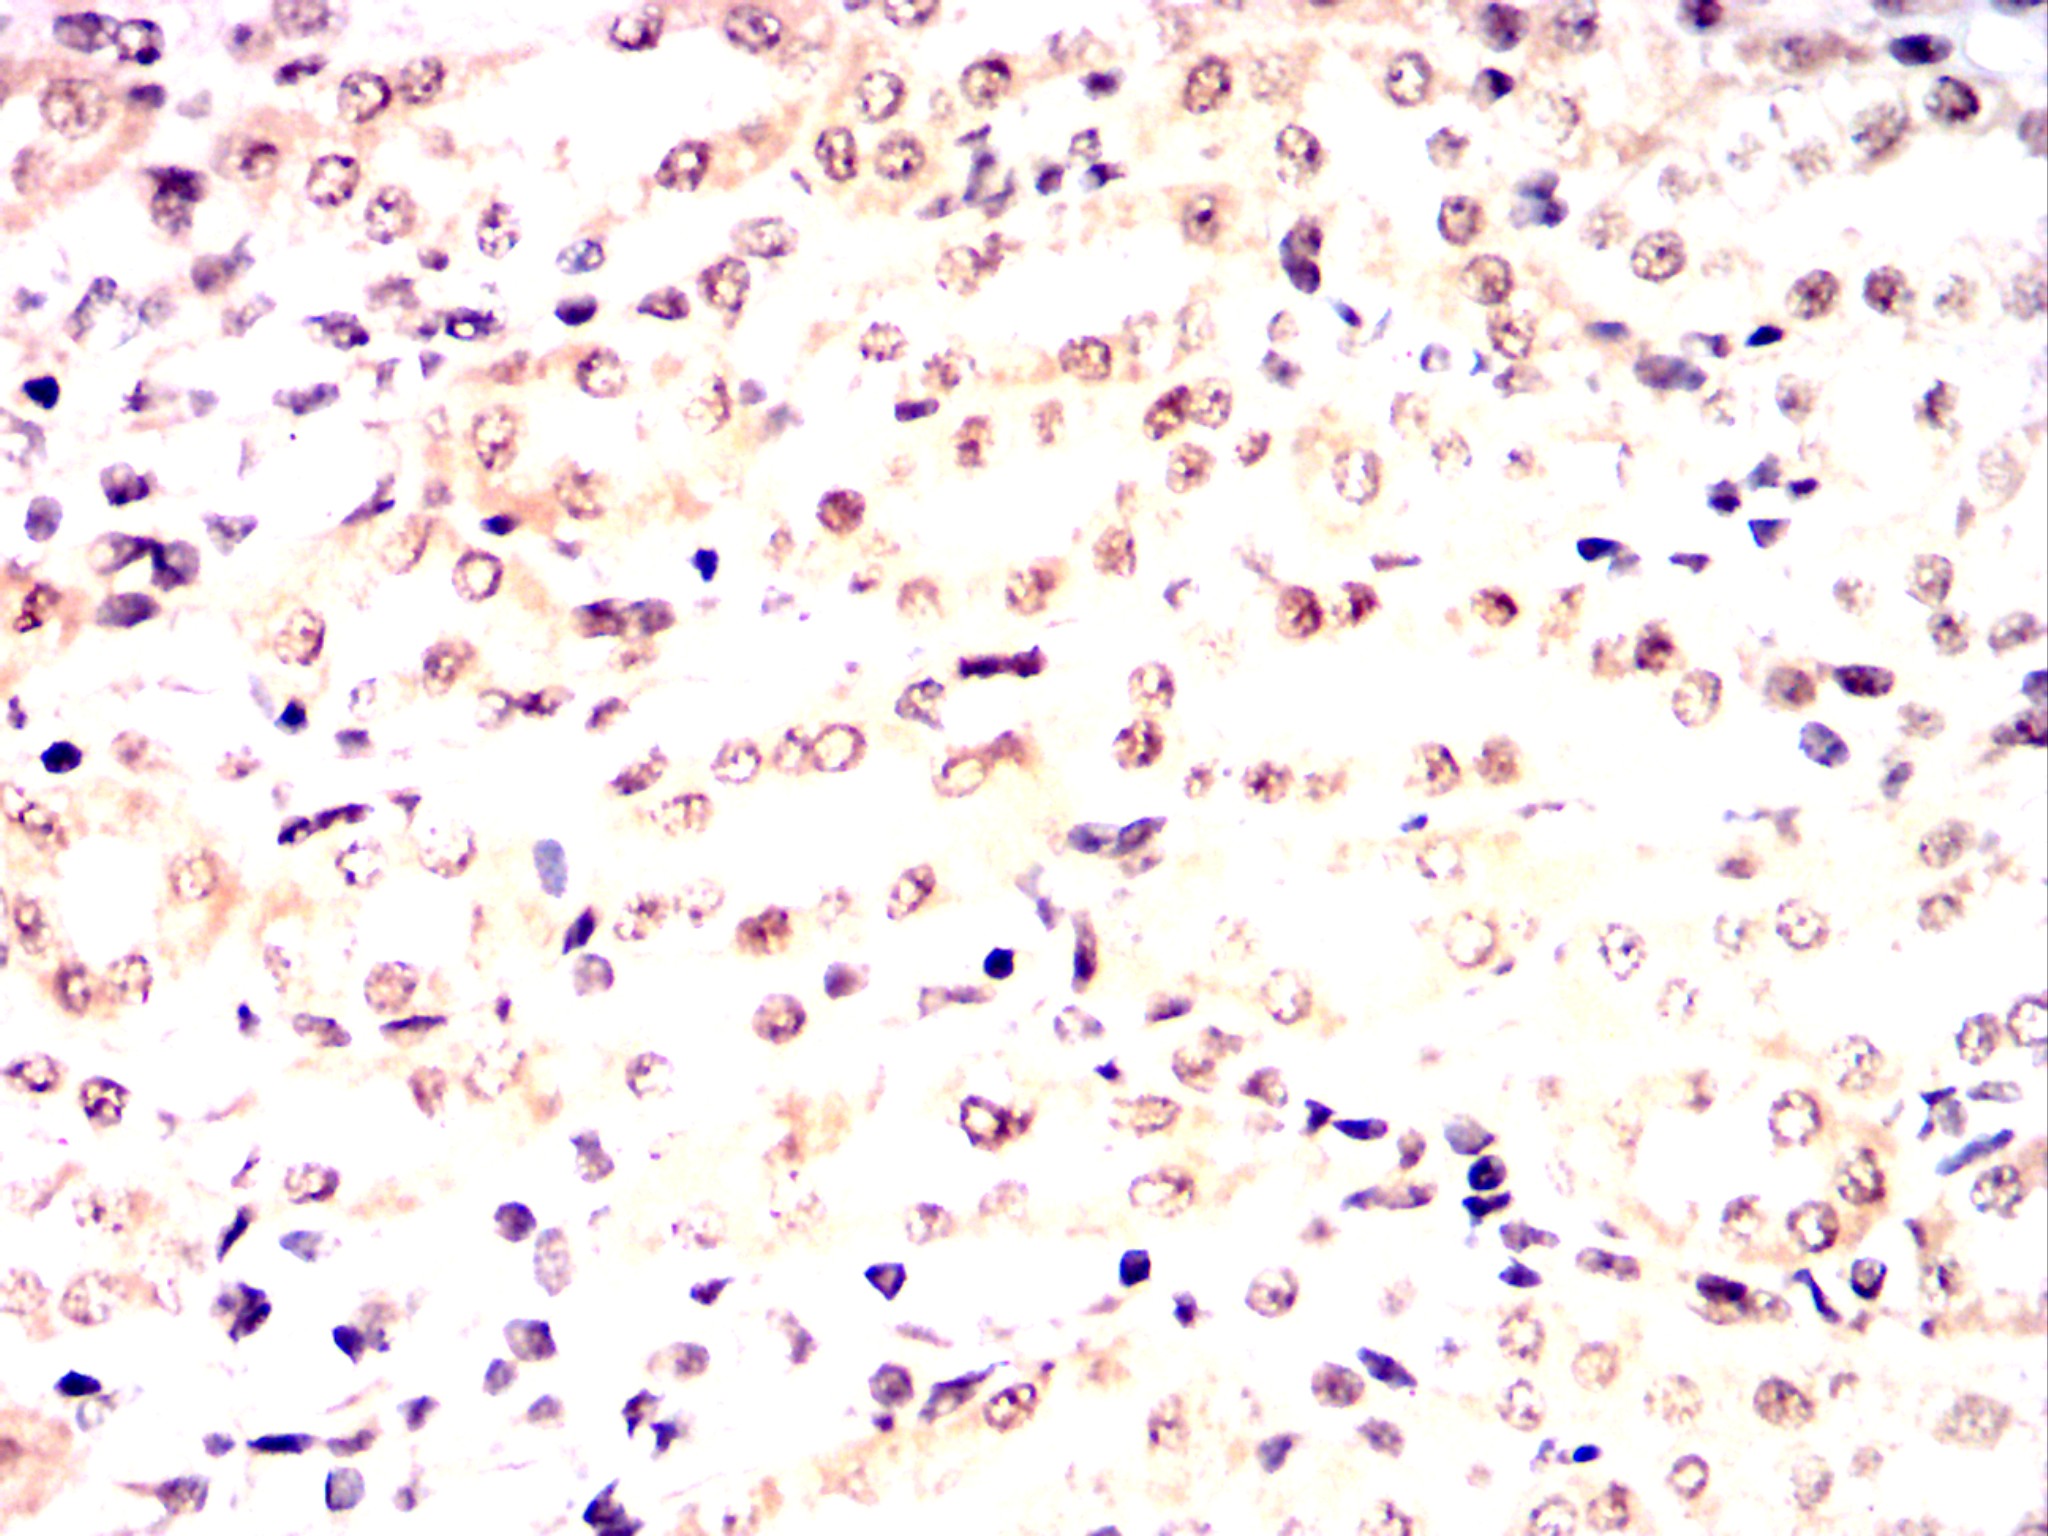

Immunohistochemical analysis of paraffin-embedded human brain tissues (left) and esophageal cancer tissues (right) using CDK9 mouse mAb with DAB staining.